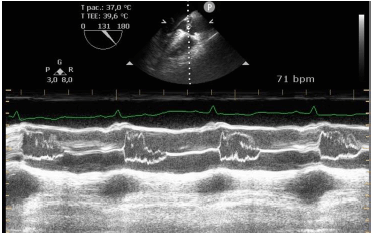

Identifique a condição patológica evidenciada na figura a seguir.